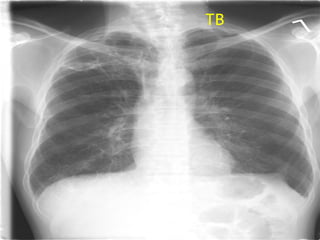

Miliary TB Snow Storm Apperance

TB